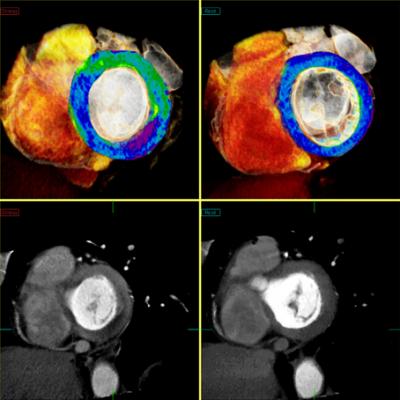

March 12, 2014 — The U.S. Food and Drug Administration (FDA) cleared Toshiba’s CT Myocardial Perfusion capability. Available on Toshiba’s Aquilion One and Aquilion OneVison Edition CT systems, Myocardial Perfusion allows clinicians to visualize myocardial ischemia with CT, providing a clinical and operational solution to make work flow.

The Myocardial Perfusion on Toshiba’s 320-detector-row CTs shows blood flow and anatomy within the coronary arteries to help determine the viability of the heart muscle. This enables clinicians to make faster and more accurate decisions on whether to undergo revascularization of coronary blockages. Toshiba’s CT Myocardial Perfusion puts patient experience first with shorter exam times and significantly lower radiation exposure.